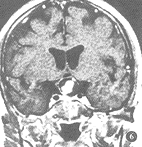

2.2.2 MR征象:病灶呈圆形或类圆形,5例中4例边界清晰可辨,在T1WI及T2WI上病灶内均有不同大小的“流空”现象所致的MR信号缺失区,呈黑色阴影,T2WI上黑色区域大于T1WI所显示的范围,周边呈混杂信号,混杂信号的大部分在T1WI上较脑灰质信号稍高,在T2WI上稍低于脑灰质。增强MR扫描可见部分混杂信号有轻度强化现象,1例见瘤壁明显强化(图3~6)。

图5 右颈内动脉巨大动脉瘤伴血栓形成。冠状面SE序列T1WI示鞍内占位,内有不规则“流空”信号及混杂信号

图6 图5病例增强T1WI示瘤壁及瘤腔内混杂信号有强化表现